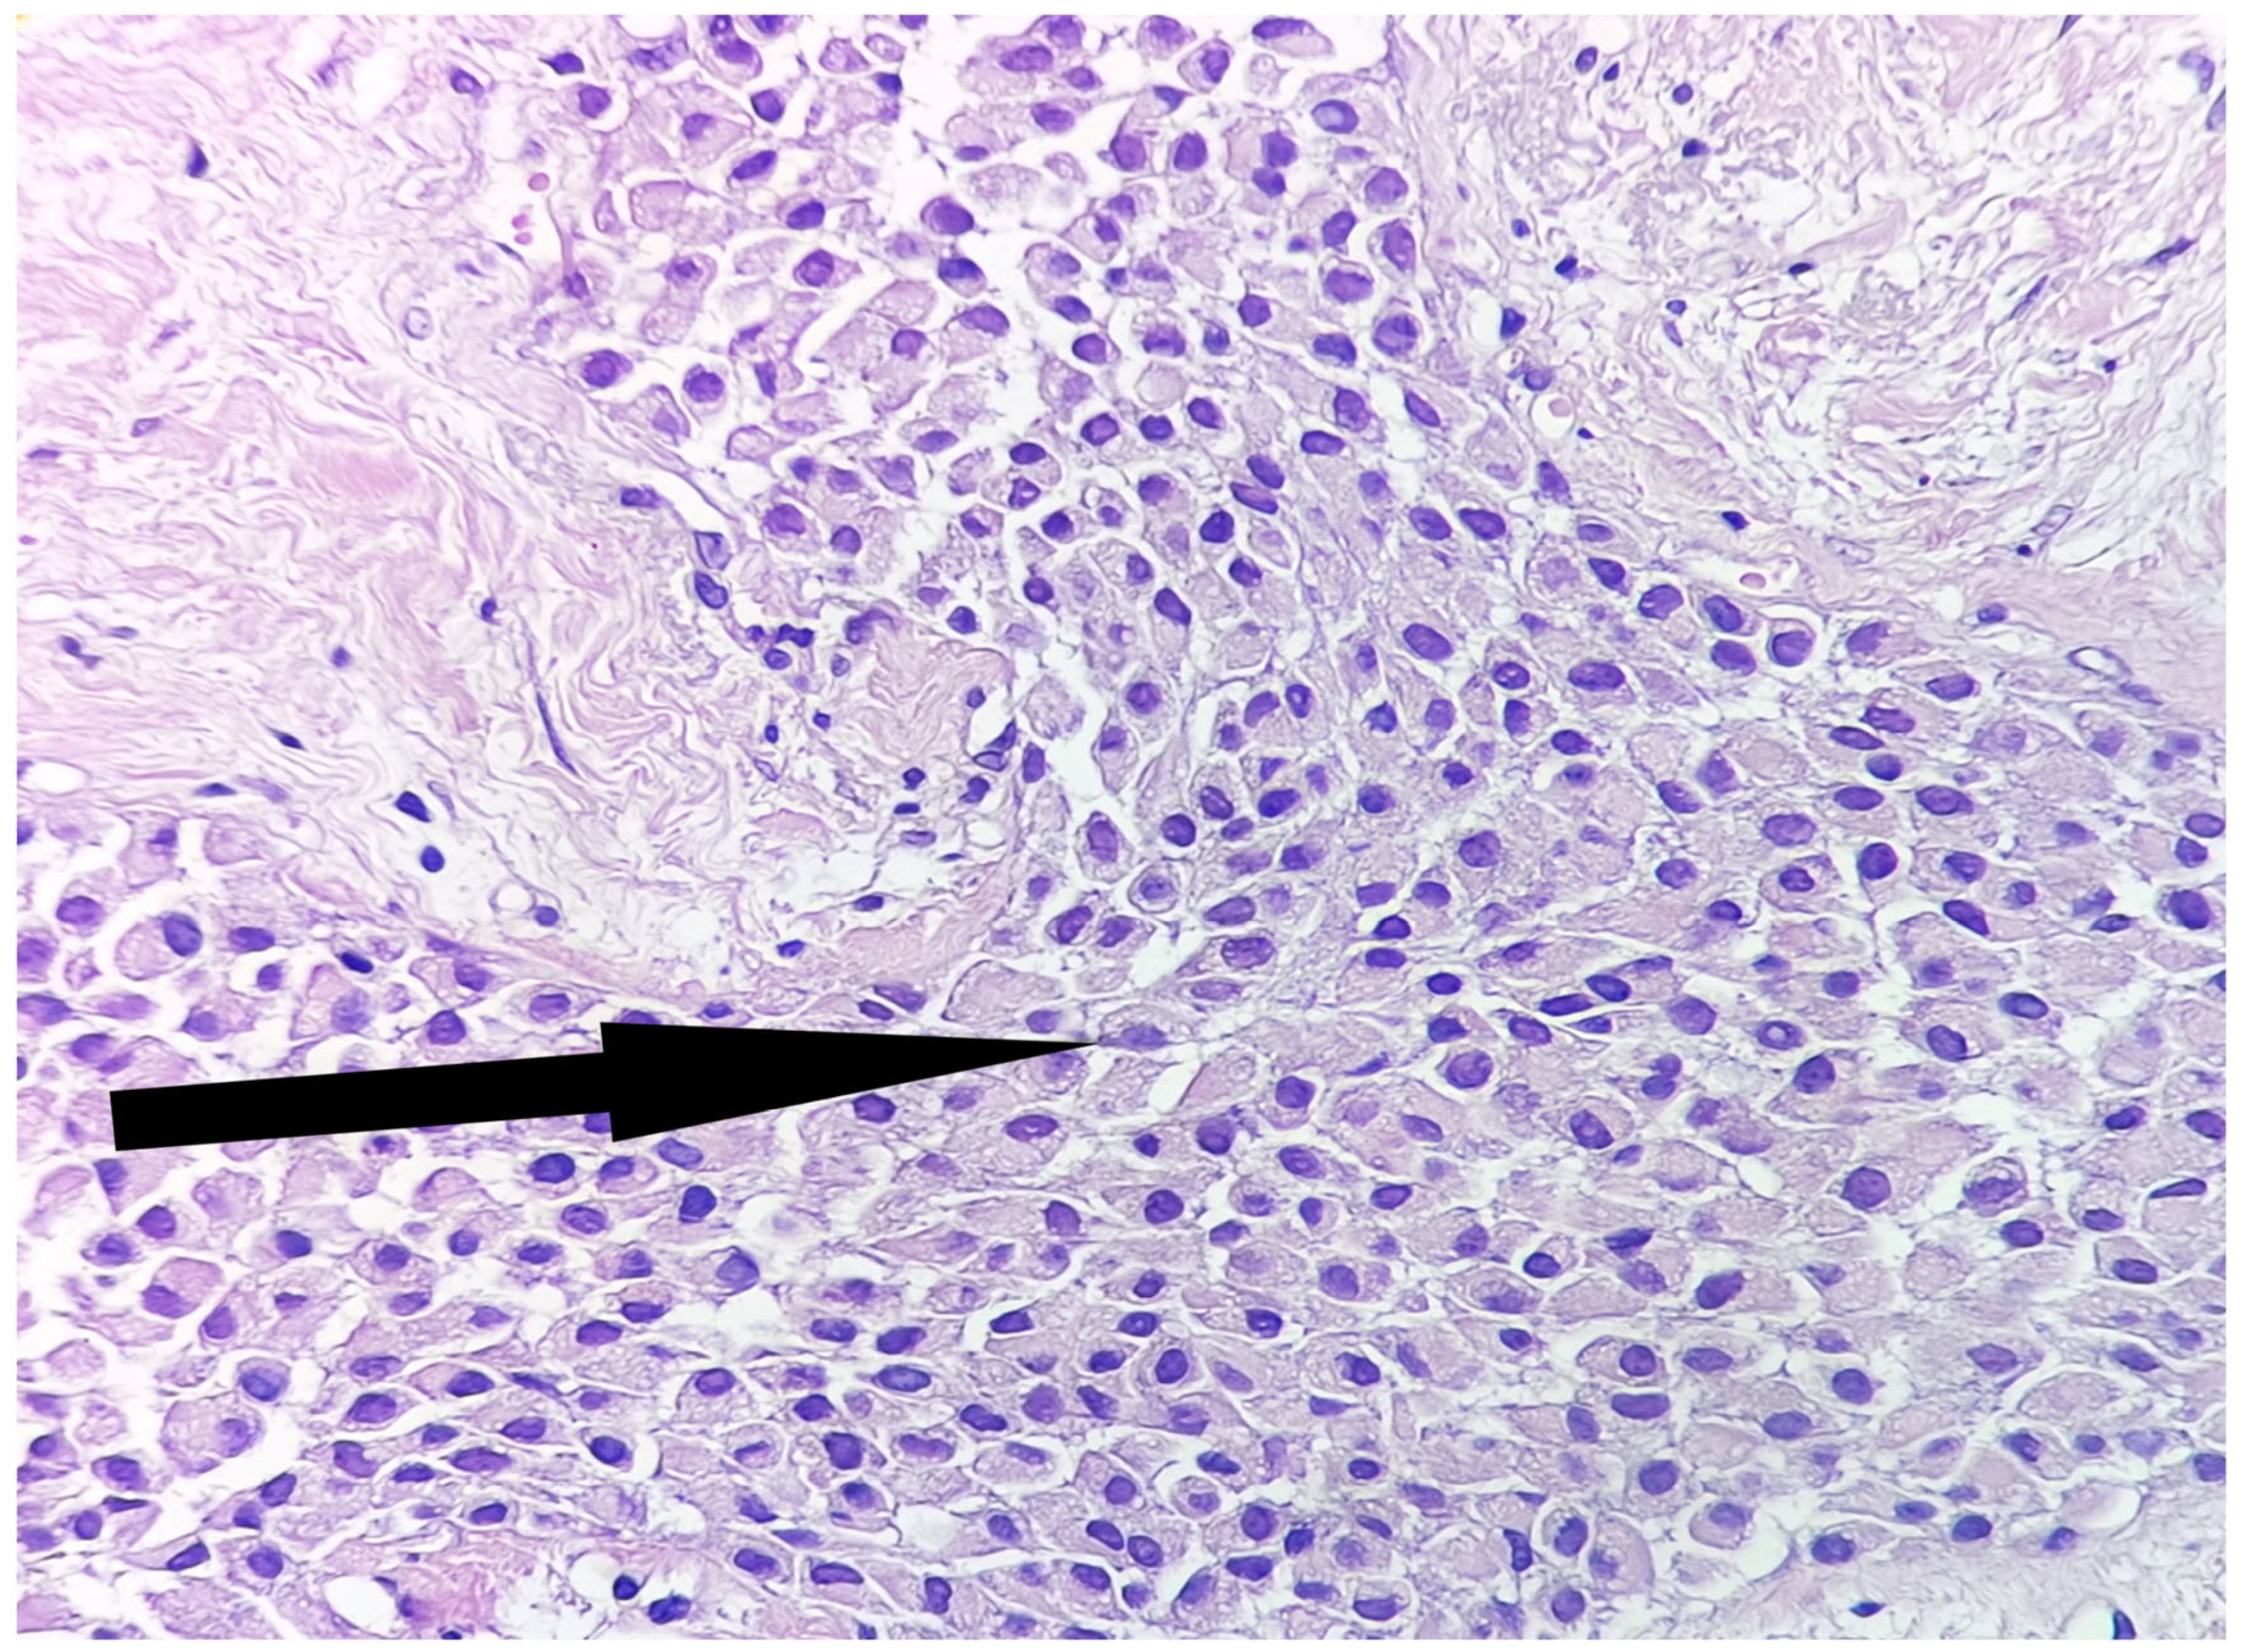

2. Case Report